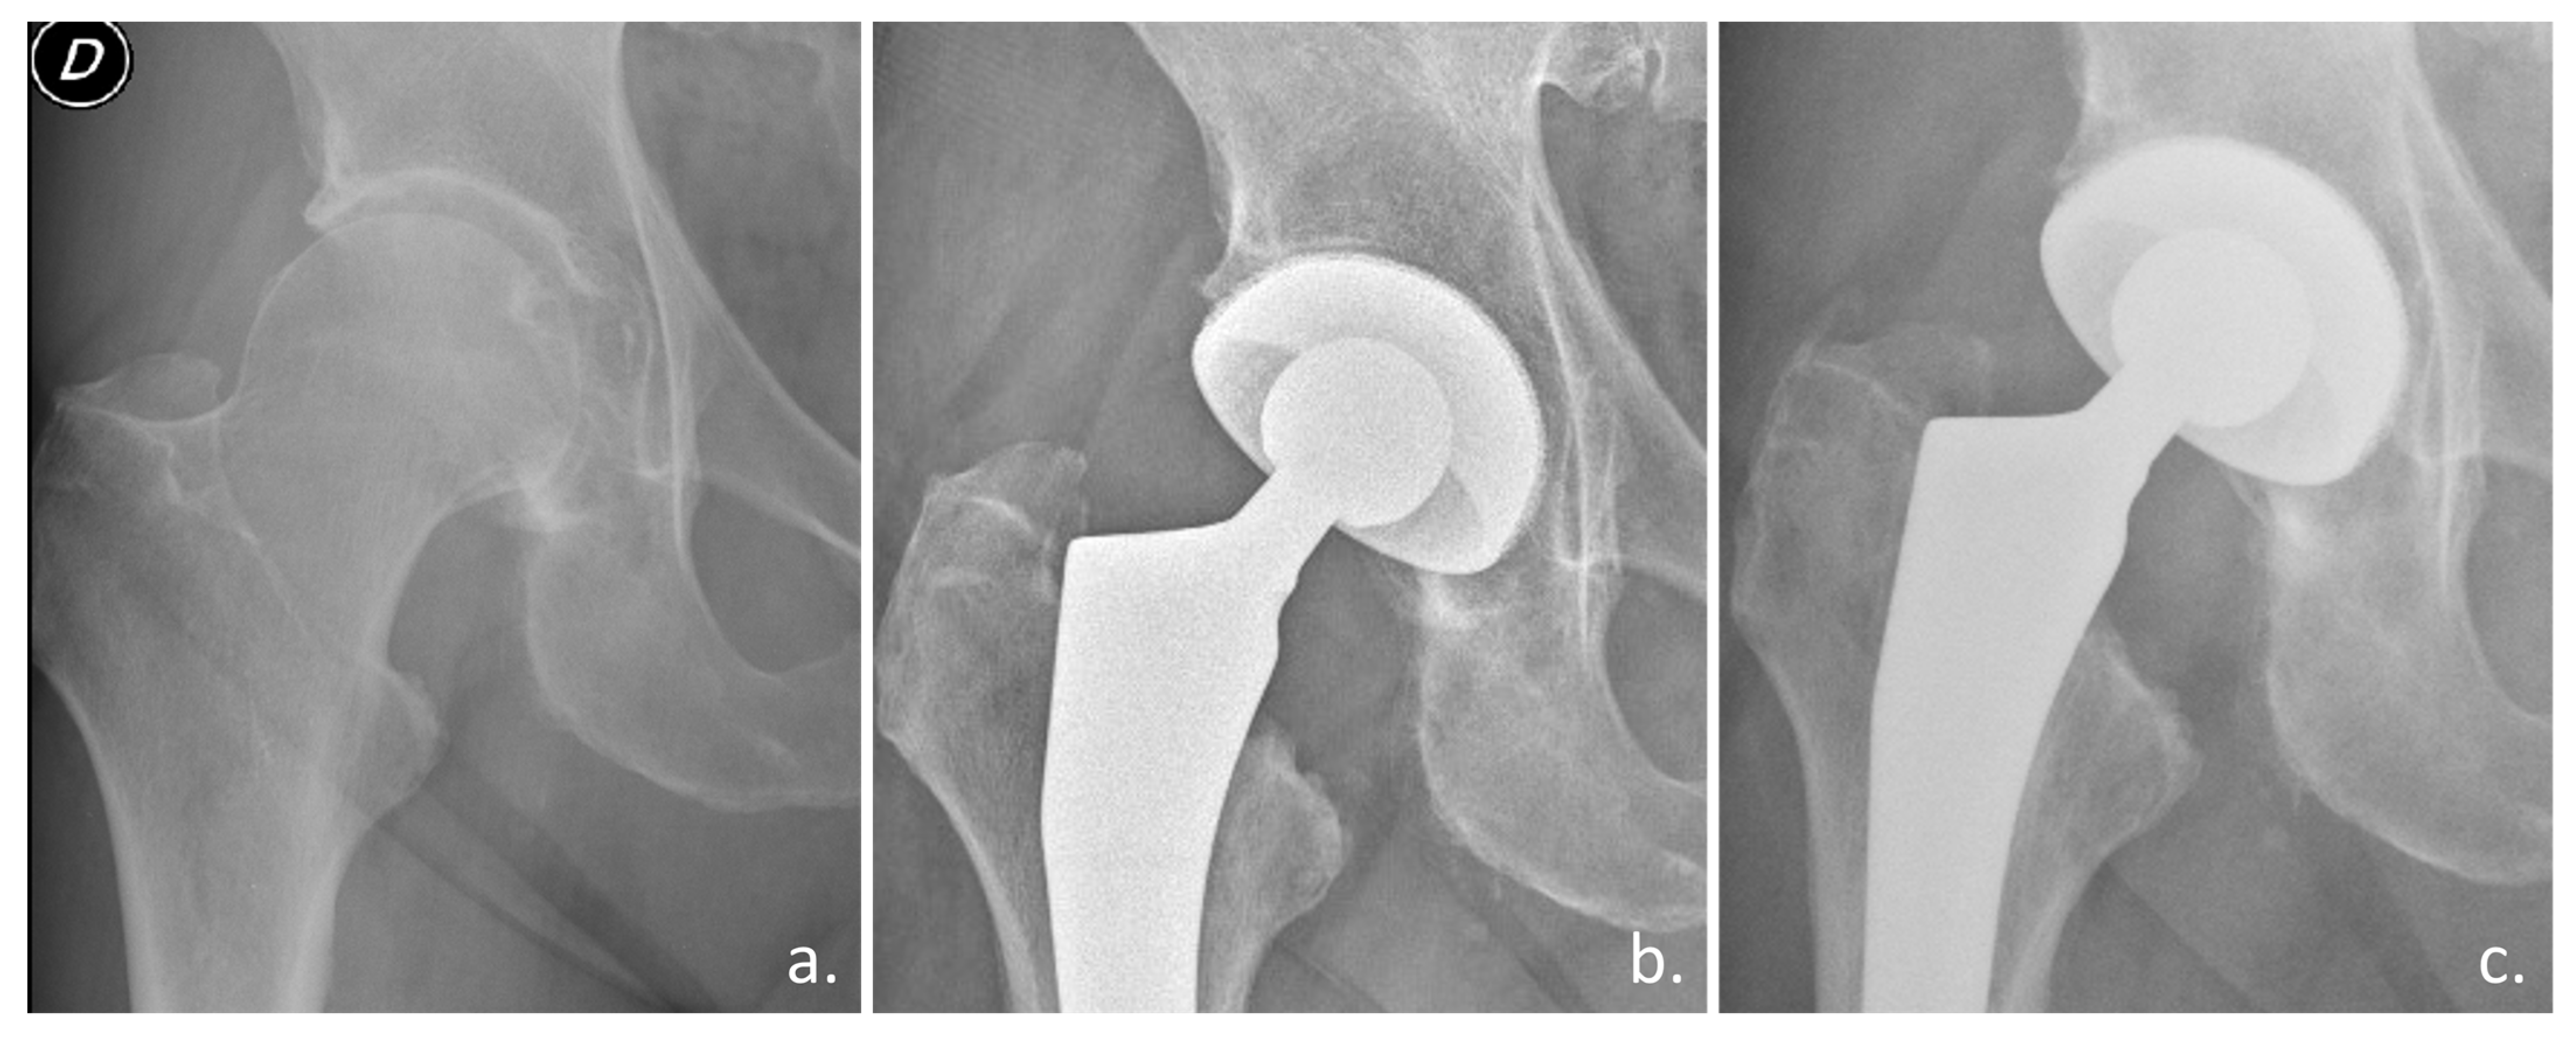

Preliminary clinical studies confirmed the osseointegration ability of a novel highly porous titanium DMC used in elective and trauma THA (Figure 4) [57,58].

Figure 4. Clinical case with the Acorn Traser dual mobility cup. Courtesy of the Dept. of Orthopaedic Surgery of Ospedale Maggiore Carlo Alberto Pizzardi. A 76-year-old man with (a) right hip osteoarthritis, a 26 kg/cm2 BMI, and a history of diabetes, hypertension, benign prostatic hyperplasia (D indicates the right side). (b) One-year after the procedure, the cup appears well osseointegrated. (c) After three years, the patient could walk unaided and had experienced no episodes of subluxation.